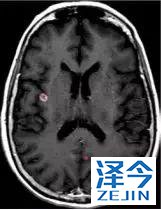

一位77岁的女性患有EPS15-NTRK1 IV期非小细胞肺癌,我们可以看到她的双肺满是病灶,并且出现了肝脏和脑转移,可以说是非常非常晚期了,

开始使用larotrectinib 100 mg BID并持续治疗,

第3周期开始:

肺靶病变达到缓解,我们可以明显的看到前后的图像,病灶明显缩小了,

脑转移病变显示缩小了95%!

初始, 2018年6月 3周期 2018年8月